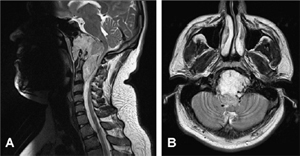

CT scan revealed a large destructive bony lesion measuring 8 cm by 6 cm by 5 cm involving the clivus and extending inferiorly to C3. There was significant compression of the brain stem, upper cervical cord and the right hypoglossal nerve, with occlusion of the right C1/2 and C2/3 intervertebral foramina. T2-weighted MRI revealed a hyperintense mass consistent with a clival chordoma (Fig. 1).

Fig. 1. (A) Sagittal and (B) axial T2-weighted MRI of the clival chordoma showing significant compression of the spinal cord and brainstem plus destruction of cervical vertebra.